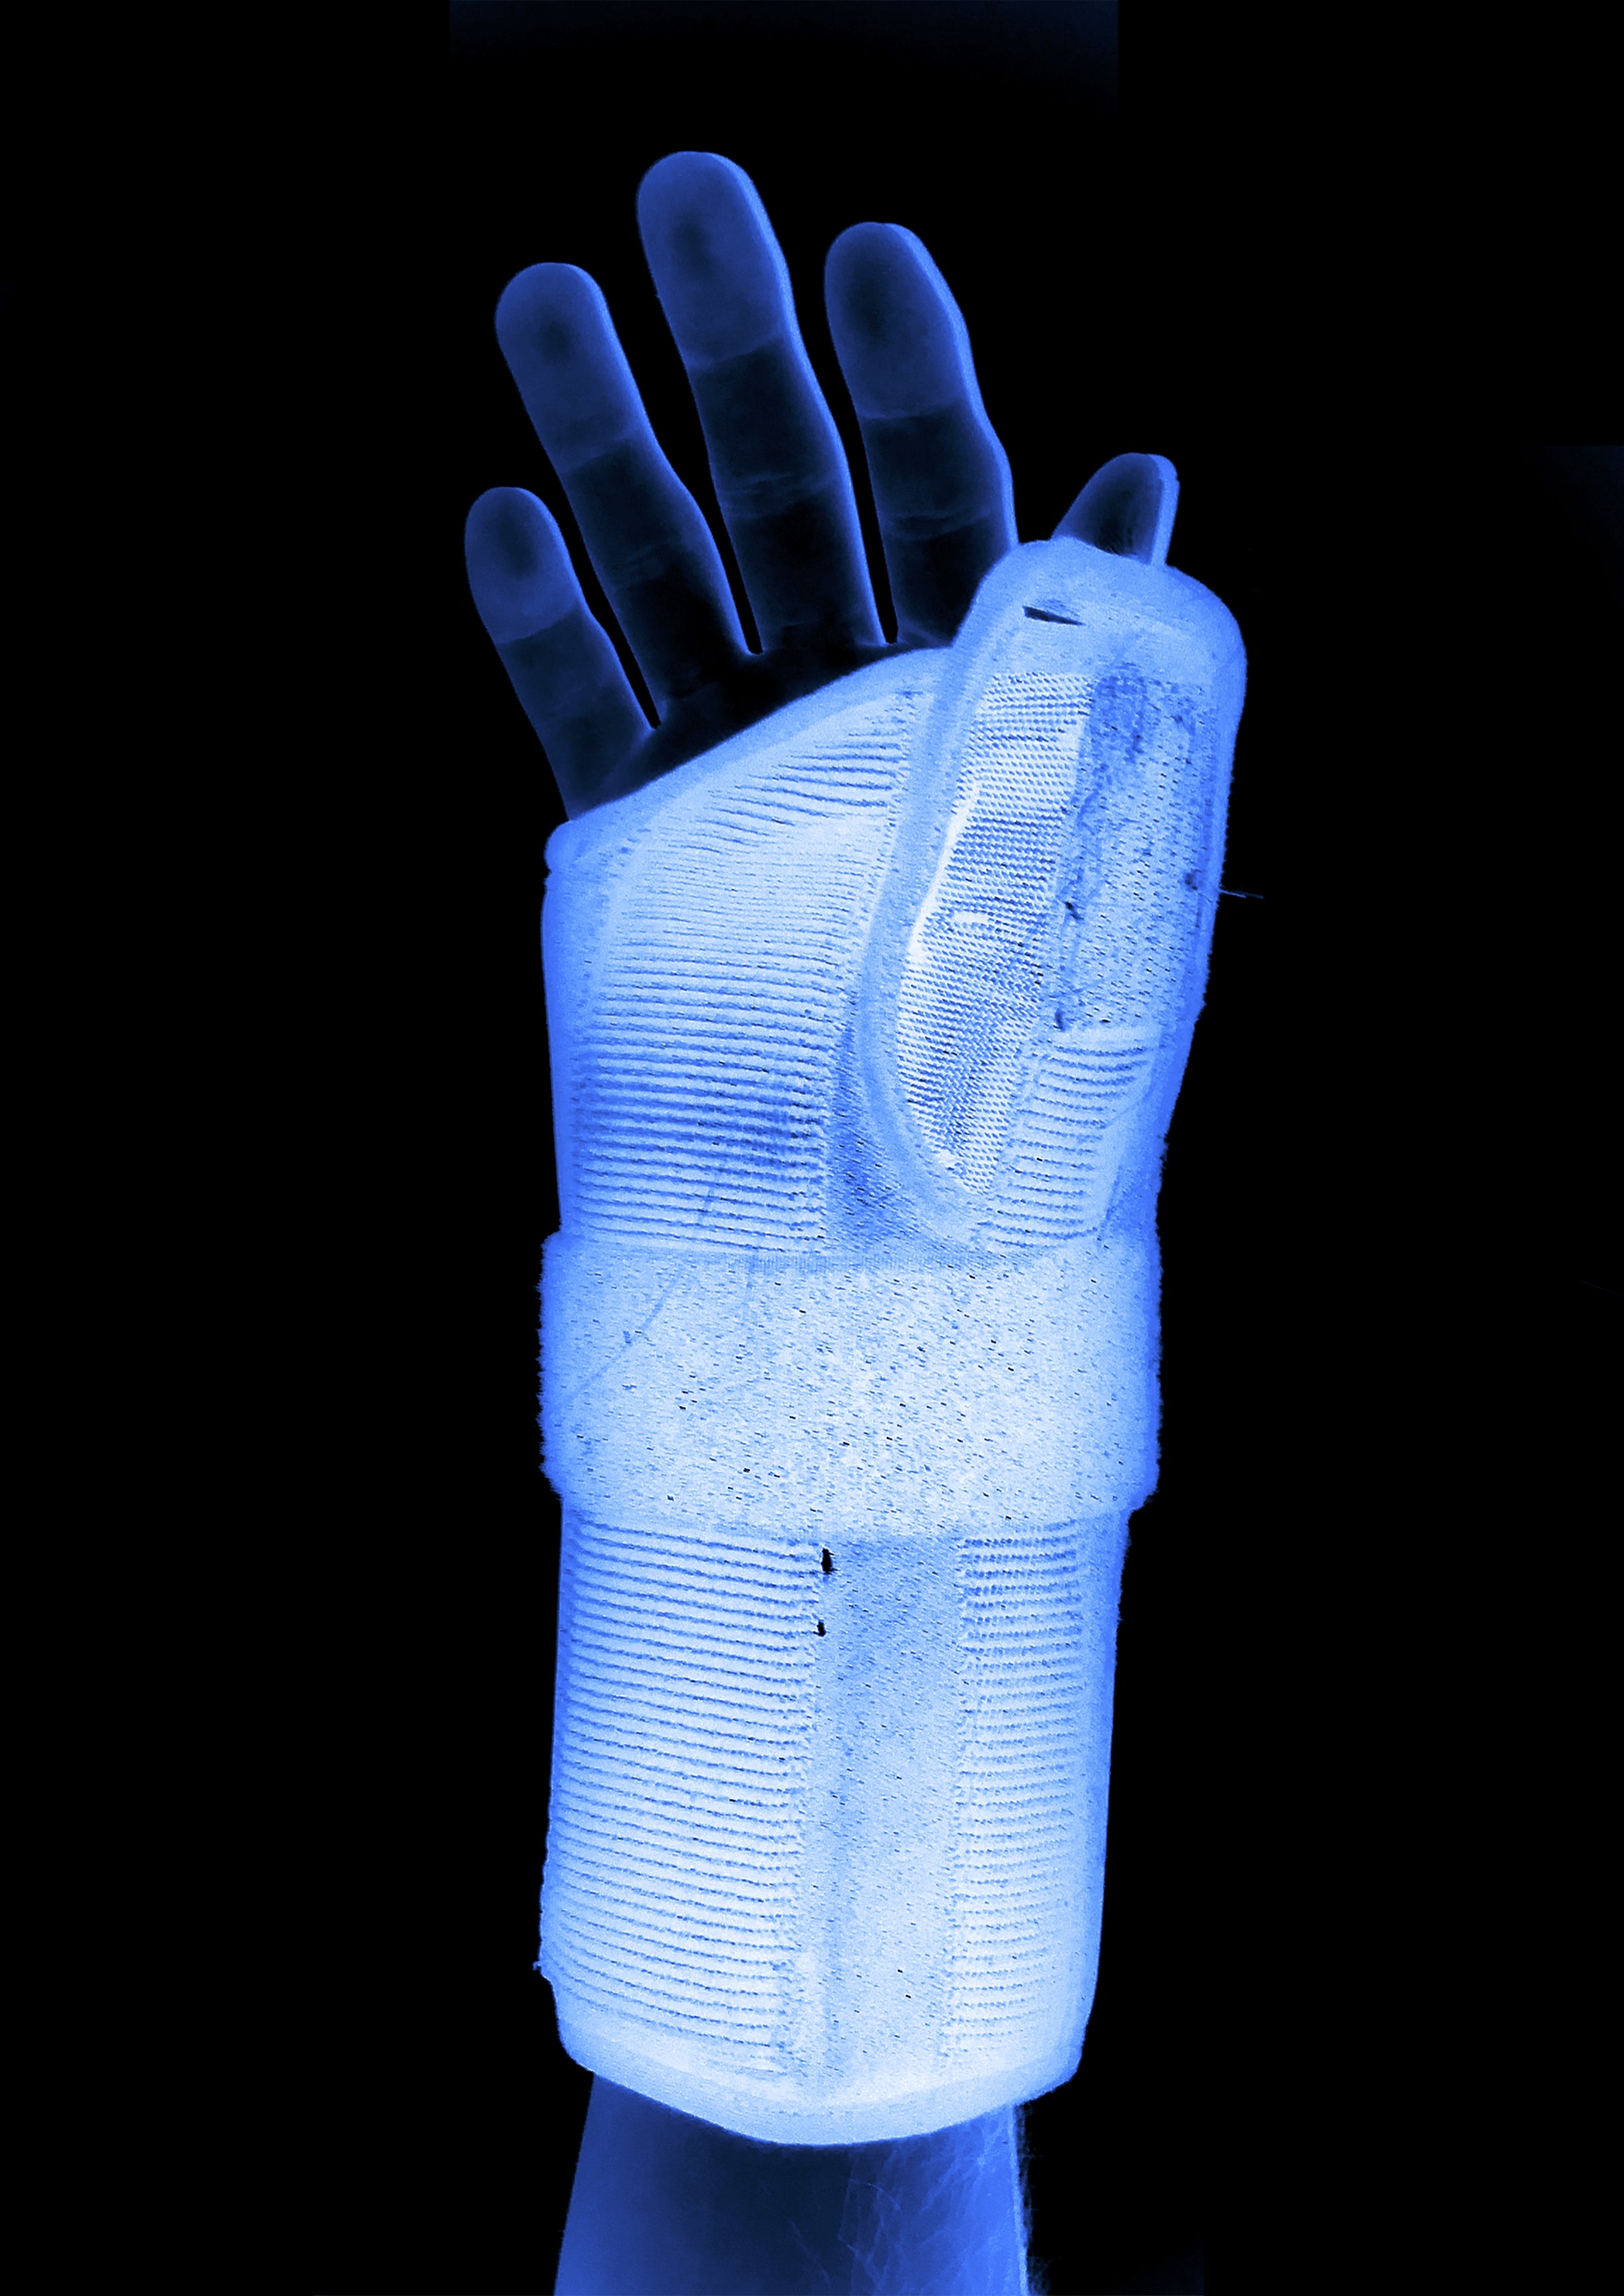

Documentation of Various Indicidents, Found objects, Crutches, Plaster,

Medical Wrap, Moon Boot, House Paint, Car Mats, Wetsuit, Projection, Casts, Video Work Forensics investigates trauma both physical and mental and how the two might interact through objectivity.